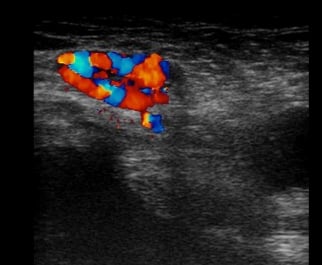

Shown here is a vascular nodule (varicosis) in the groin of a pregnant patient. She came to us with a suspicion of inguinal hernia because of the presentation of an easily palpable swelling in the groin that was not painful.

In contrast to the inguinal hernia, this protrusion cannot be pushed away when the patient is standing. When the patient is lying down, the increase in blood flow in the mother ligament (ligamentum rotundum) recedes markedly due to improved drainage in the veins and is often no longer palpable.

The bright colors represent the blood flow in the Doppler examination, which can be diagnosed by any doctor within a few seconds. This finding recedes completely after delivery and the resulting decrease in venous congestion and must never be operated on.